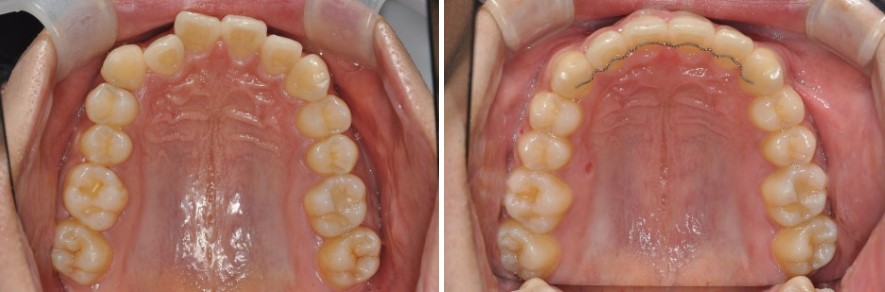

위·아래 치아 크기 비율을 맞추기 위해

위턱과 아래턱의 치아 크기 비율이 맞지 않는 경우에도 교합 형성이 어려울 수 있습니다.

예를 들어,

윗니 중 작은 앞니(측절치)가 유난히 작은 경우,

이런 경우:

실제 예를 들면,

즉, 어떤 경우는 보철 + 교정, 어떤 경우는 치간삭제 + 교정만으로도 해결이 가능하며,